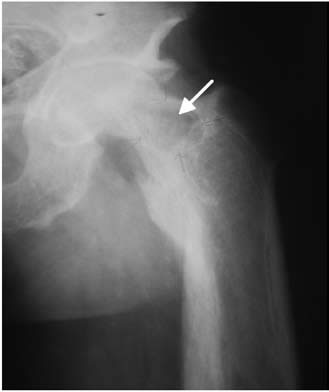

Hombre de 37 años de edad, con insuficiencia renal crónica por enfermedad de Berger, en hemodiálisis trisemanal desde los 20 años de edad. A los 21 años se efectúa trasplante renal de donante vivo. Reingresó a hemodiálisis por rechazo del injerto a los 24 años de edad. Evolucionó con HPT 2° progresivo (PTH: 4414 pg/mL), por lo que en otro centro asistencial se efectuó, a los 29 años, paratiroidectomía de las dos glándulas superiores. A pesar de esto, el HPT 2° no se modificó, presentando a los 34 años de edad fractura no traumática de fémur izquierdo. En mayo de 2008, es visto en nuestro servicio con intenso dolor en la cadera izquierda; el estudio radiológico evidenció un gran tumor pardo en el cuello femoral izquierdo de 5 cm de diámetro (Figura 1). La concentración de PTH era 4658 pg/mL.